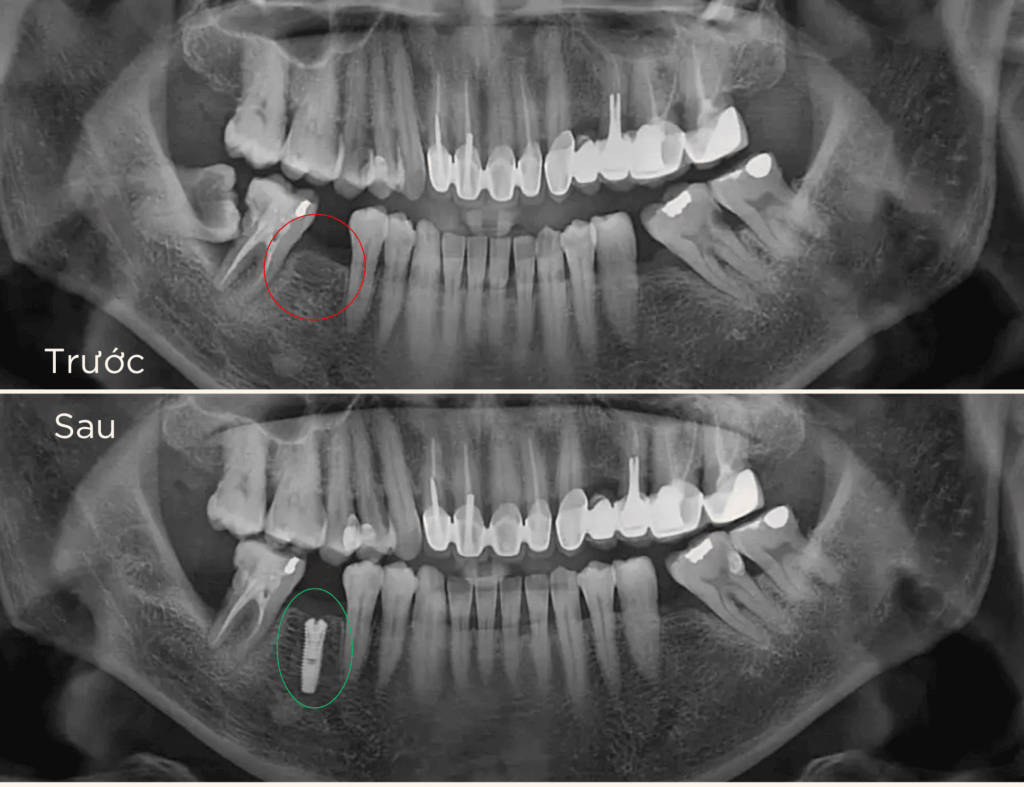

Trồng răng Implant 1 răng là phương pháp phục hồi răng mất tiên tiến, sử dụng trụ chụ chân răng nhân tạo – Implant từ titanium cấy vào xương hàm để thay thế chân răng đã mất. Sau đó, một mão răng sứ được gắn lên trụ, tạo ra chiếc răng mới với hình dáng và chức năng giống như răng thật.

– Mất 1 răng gần đây : Muốn khôi phục lại để ăn nhai thoải mái, giữ nụ cười đẹp và tự tin.

– Mất răng lâu năm: Răng xung quanh xô lệch, sai khớp cắn, ảnh hưởng ăn nhai và thẩm mỹ.